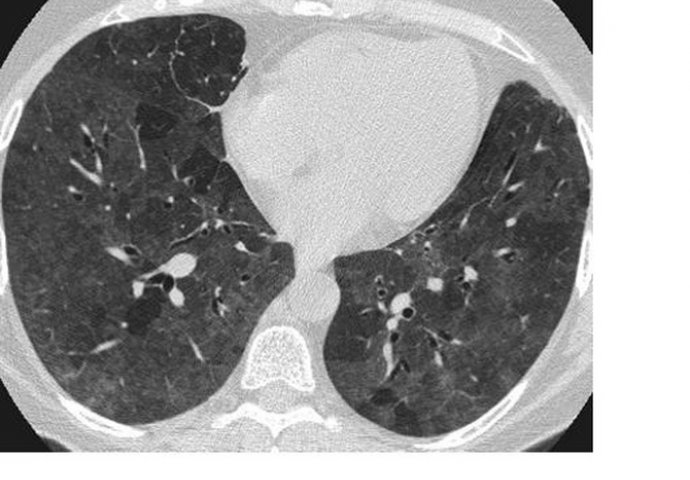

Naučni članak objavljen u Annals of Internal Medicine kaže da su snimci pluća asimptomatskih pacijenata pokazali određene abnormalnosti na plućima.

Tačnije, našli su ono što radiolozi nazivaju "mliječno staklo" koje se uglavnom javlja u donjem dijelu pluća, ali to ne mora uvijek da bude slučaj. Ovaj naučni tekst tvrdi da se "mliječno staklo" javlja u 54 odsto asimptomatskih pacijenata.

- "Mlečna pluća" nisu neuobičajena i postoji nekoliko uzroka za njih. Međutim, mliječno staklo nastalo usljed Kovida-19 je drugačije. Oblik je okrugao i raspoređeni su po krajevima pluća, što je neuobičajeno - kaže Adam Bernejm, radiolog iz Mount Sinai bolnice u Njujorku.